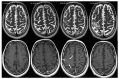

Background. Natalizumab treatment is frequently discontinued and replaced by alternative medication in multiple sclerosis (MS) patients having a high risk of progressive multifocal leukoencephalopathy (PML). Case Presentation. We report a PML case that was missed on magnetic resonance imaging (MRI) at the time Natalizumab treatment was discontinued. The patient subsequently developed a PML-immune reconstitution inflammatory syndrome after the initiation of Fingolimod treatment, suggesting that immune reconstitution may occur even during Fingolimod induced lymphopenia. Conclusion. This report highlights the need for strict drug surveillance using MRI of Natalizumab-associated MS patients at the time of drug discontinuation and beyond. This is important with respect to pharmacovigilance purposes not only for Natalizumab, but also for alternative drugs used after Natalizumab discontinuation.